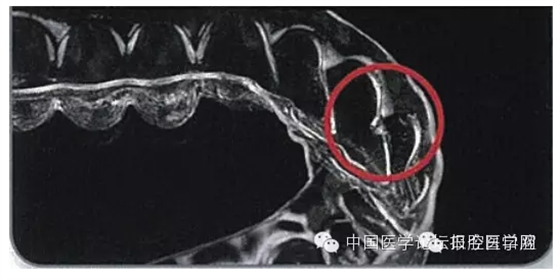

一類是基于石膏模型排牙后,通過熱壓成型技術(shù)加工矯治器傳統(tǒng)無托槽隱形矯治技術(shù)。這類技術(shù)也有所差異,一種以Essix系統(tǒng)(圖1)為代表。此技術(shù)是在翻制的石膏模型上移動牙齒后設(shè)計制作單個矯治器來矯治輕度的錯畸形,其移動牙齒的方式是對擬移動的牙齒進(jìn)行修整和緩沖處理,通過Hilliard熱成型鉗改變矯治器形狀或在牙面上粘接樹脂突給牙齒加力,也可通過矯治器上的牽引鉤進(jìn)行彈性牽引,逐步實現(xiàn)牙齒移動。

圖1 Essix矯治器加力方式(鉗子加熱,測量鉗子溫度,使用加熱后的鉗子在矯治器上形成突起,矯治器完成)